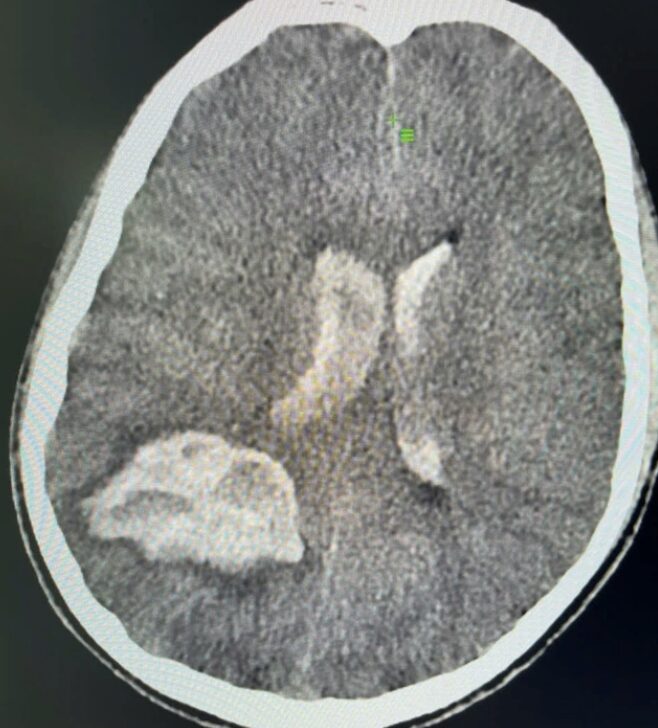

Theo thông tin từ các bác sĩ, bệnh nhân P.A.S được chỉ định chụp cắt lớp vi tính sọ não ngay khi nhập viện. Kết quả cho thấy em bị xuất huyết não lan vào não thất – tình trạng cấp cứu nguy hiểm, có thể đe dọa tính mạng nếu không được xử trí kịp thời.

Bệnh nhân được xác định xuất huyết não qua hình ảnh cắt lớp vi tính